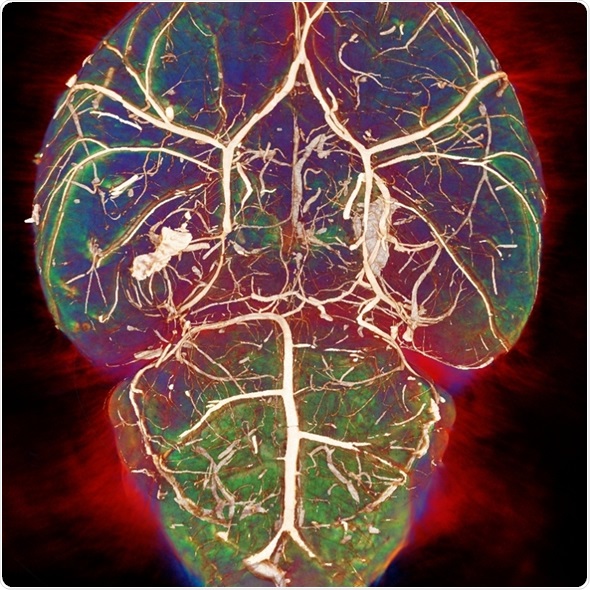

Each modality looks at tissue in a different way. For example, MRI has very good soft tissue contrast and there is a number of parameters that are associated with different pathologies.

For example, there are T1 and T2 changes in cancer and neurodegenerative diseases, whereas, with a modality like CT, there's less soft tissue contrast and it would be used more to look at things like bone structure. It uses a different type of contrast and produces images through a different physical mechanism.

By using different modalities, we can get much more information compared with using only one modality.

The MRI has a very good soft tissue contrast. The parameters that I generally look at using MRI are called T1 and T2. These vary in different tissues, obviously, but also across different pathologies. MRI provides very high sensitivity to these pathologies, which can't be seen using other modalities.